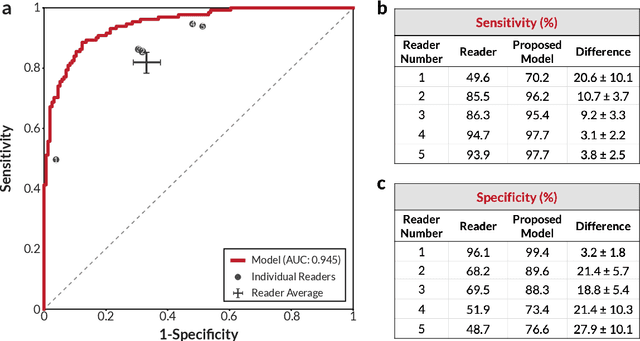

Robust breast cancer detection in mammography and digital breast tomosynthesis using annotation-efficient deep learning approach

Dec 27, 2019

Breast cancer remains a global challenge, causing over 1 million deaths globally in 2018. To achieve earlier breast cancer detection, screening x-ray mammography is recommended by health organizations worldwide and has been estimated to decrease breast cancer mortality by 20-40%. Nevertheless, significant false positive and false negative rates, as well as high interpretation costs, leave opportunities for improving quality and access. To address these limitations, there has been much recent interest in applying deep learning to mammography; however, obtaining large amounts of annotated data poses a challenge for training deep learning models for this purpose, as does ensuring generalization beyond the populations represented in the training dataset. Here, we present an annotation-efficient deep learning approach that 1) achieves state-of-the-art performance in mammogram classification, 2) successfully extends to digital breast tomosynthesis (DBT; "3D mammography"), 3) detects cancers in clinically-negative prior mammograms of cancer patients, 4) generalizes well to a population with low screening rates, and 5) outperforms five-out-of-five full-time breast imaging specialists by improving absolute sensitivity by an average of 14%. Our results demonstrate promise towards software that can improve the accuracy of and access to screening mammography worldwide.